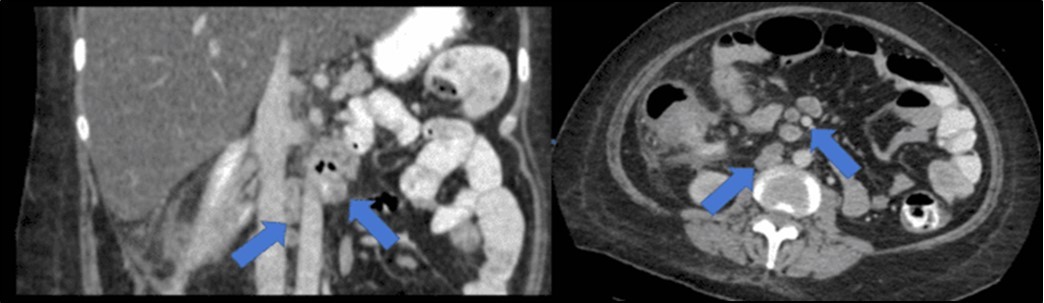

There was no evidence of malignancy or IBD seen during both endoscopic procedures. Computed tomography (CT) scan of the whole abdomen was done which showed inflammatory changes involving the cecum and adjacent duodenum and ileum with coloenteric fistulae. There was noted progression of abdominal lymphadenopathies as well as ascites. Main consideration was an infectious disease process (i.e. TB) (Figure 2, Figure 3, Figure 4 to Figure 5).

Figure 4.Coronal and axial view of the abdomen, the blue arrows pointing towards the suggestive communication to the duodenum